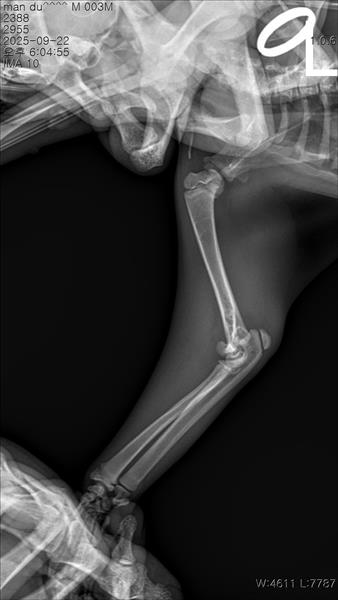

만지면 아파하길래 냅다 병원가서 엑스레이 진단을 받았어요

왼쪽 앞다리 팔꿈치 부분 성장판 골절이라고 진단을 받고 수술을 권장 받았어요..

아직 어린 우리 아이에게 이런 일이 생겨서 많이 놀라셨을 것 같아요. 말씀주신 상황과 사진을 보면 상완골 원위단, 성장판 골절이 확인됩니다.

깁스 치료는 전위가 거의 없는 "안정적" 골절에서는 가능하지만, 우리 아이의 경우 주관절의 불안정성으로 파행이 생길 수 있어 깁스만으로는 예후가 좋지 않을 듯 합니다. 깁스로 버틴다 해도 비뚤게 붙거나, 성장판 손상으로 앞다리 변형이 남을 수 있습니다.

따라서, 정확히 맞추고 고정하는 수술치료가 가장 좋은 치료 방법입니다. 나이가 어려 회복이 빠르고, 정상 보행 가능성이 높으니 수술치료를 고려해보시는 것을 권해드립니다.